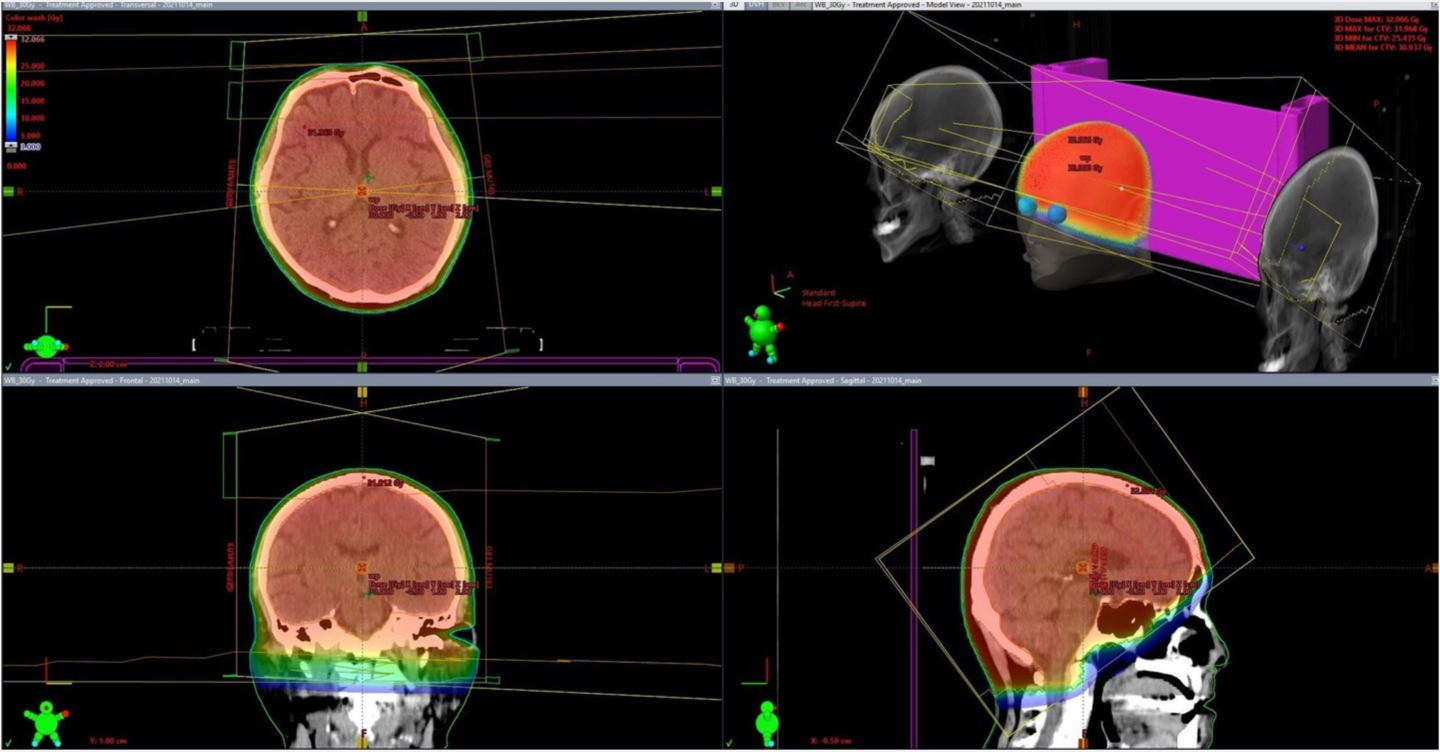

最新鋭の放射線治療装置を導入しており、強度変調放射線治療(IMRT)やピンポイントでがん組織を狙い撃ちする定位放射線治療(SRT)などを、位置照合を正確に行う画像誘導放射線治療(IGRT)により、がん組織に集中して放射線を照射することが出来ます。

健康組織への影響を最小限に抑えた、患者さんの身体に優しい治療をすることが可能です。

がんなどの治療標的を取り巻く正常組織へ放射線が当たることを避け, VMAT(強度変調回転照射), SRS(定位放射線手術), SRT(定位放射線治療), SBRT(体幹部定位放射線治療)を行っています。